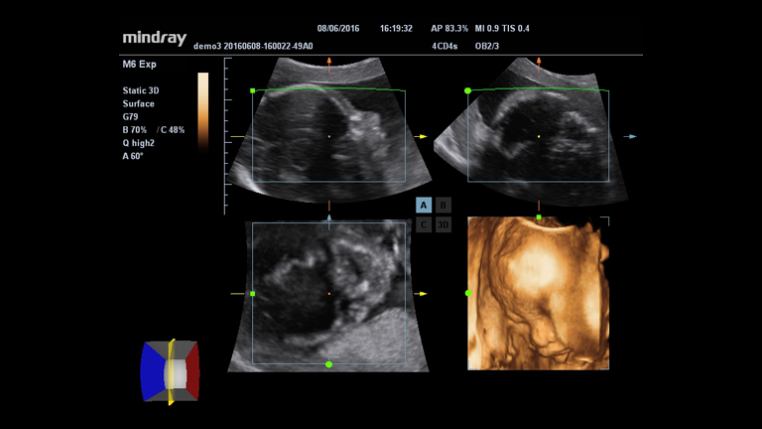

3D/4D imaging technology delivers a range of tools that help take advantage of the full value of volume data. With rich rendering modes, more information on fetus structure is made available to make a more confident diagnosis.